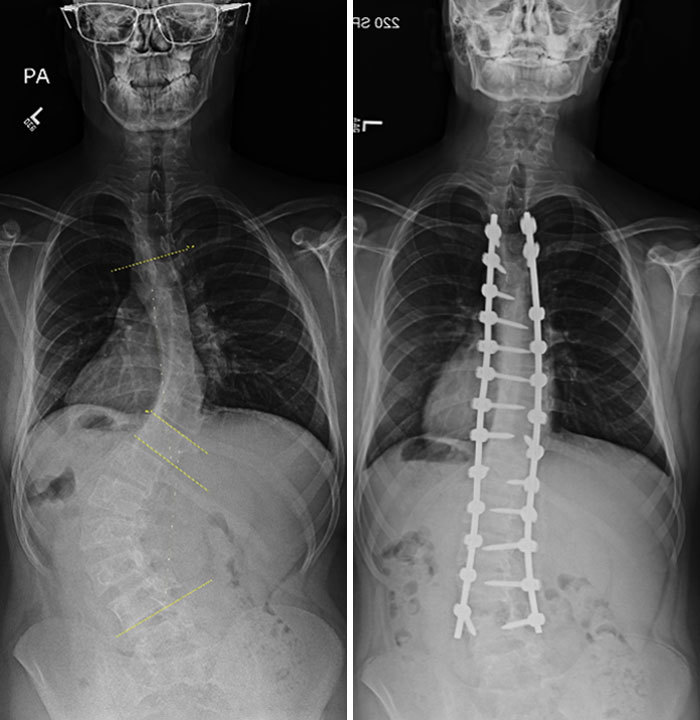

文章插图

脊柱侧弯手术 , 之前和之后